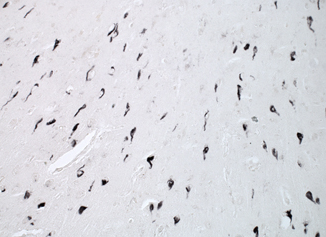

p62免疫反應(yīng)性的免疫組織化學(xué)分析存在于阿爾茨海默氏癥患者的海馬神經(jīng)元中。注意神經(jīng)原纖維纏結(jié)的強(qiáng)烈反應(yīng)(稀釋度1:1000)。顯微照片由荷蘭馬斯特里赫特大學(xué)的Fred van Leeuwen教授提供。